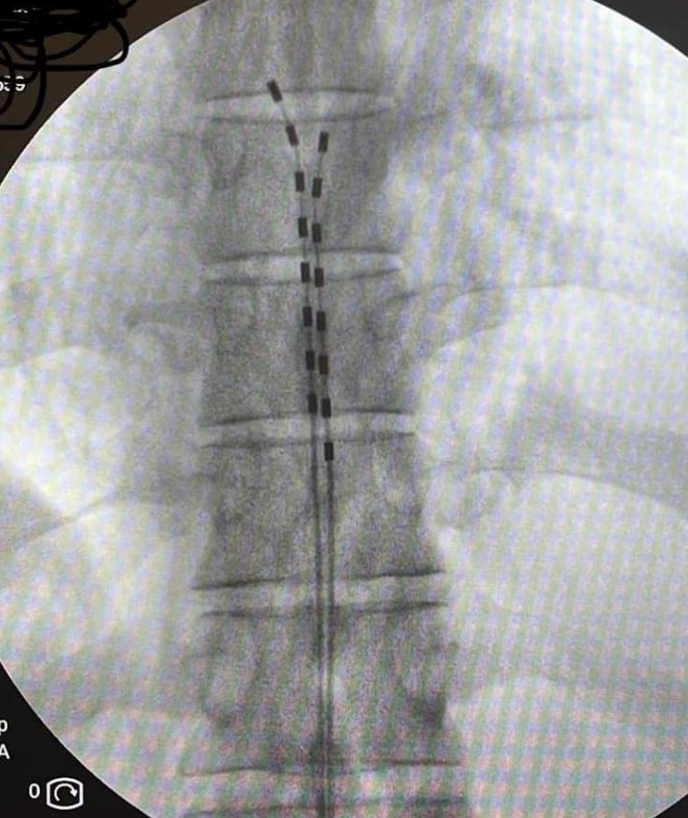

Με τον ασθενή σε πρηνή θέση, υπό τοπική αναισθησία και ακτινοσκοπική καθοδήγηση εμφυτεύονται τα ηλεκτρόδια στον επισκληρίδιο χώρο της σπονδυλικής στήλης και συνδέονται με έναν εξωτερικό διεγέρτη που δίνει τα ερεθίσματα με ένταση που επιλέγεται ανάλογα με τις ανάγκες του ασθενούς. Ο ασθενής για μια περίοδο 7-10 ημερών μπορεί να δοκιμάσει το αποτέλεσμα της διέγερσης και να κρίνει εάν αυτή καλύπτει τις ανάγκες του. Εάν η θεραπεία δεν είναι αποτελεσματική, τα ηλεκτρόδια αφαιρούνται με πολύ εύκολο τρόπο. Επί θετικής απόκρισης, έπεται η διαδικασία τελικής εμφύτευσης του συστήματος.